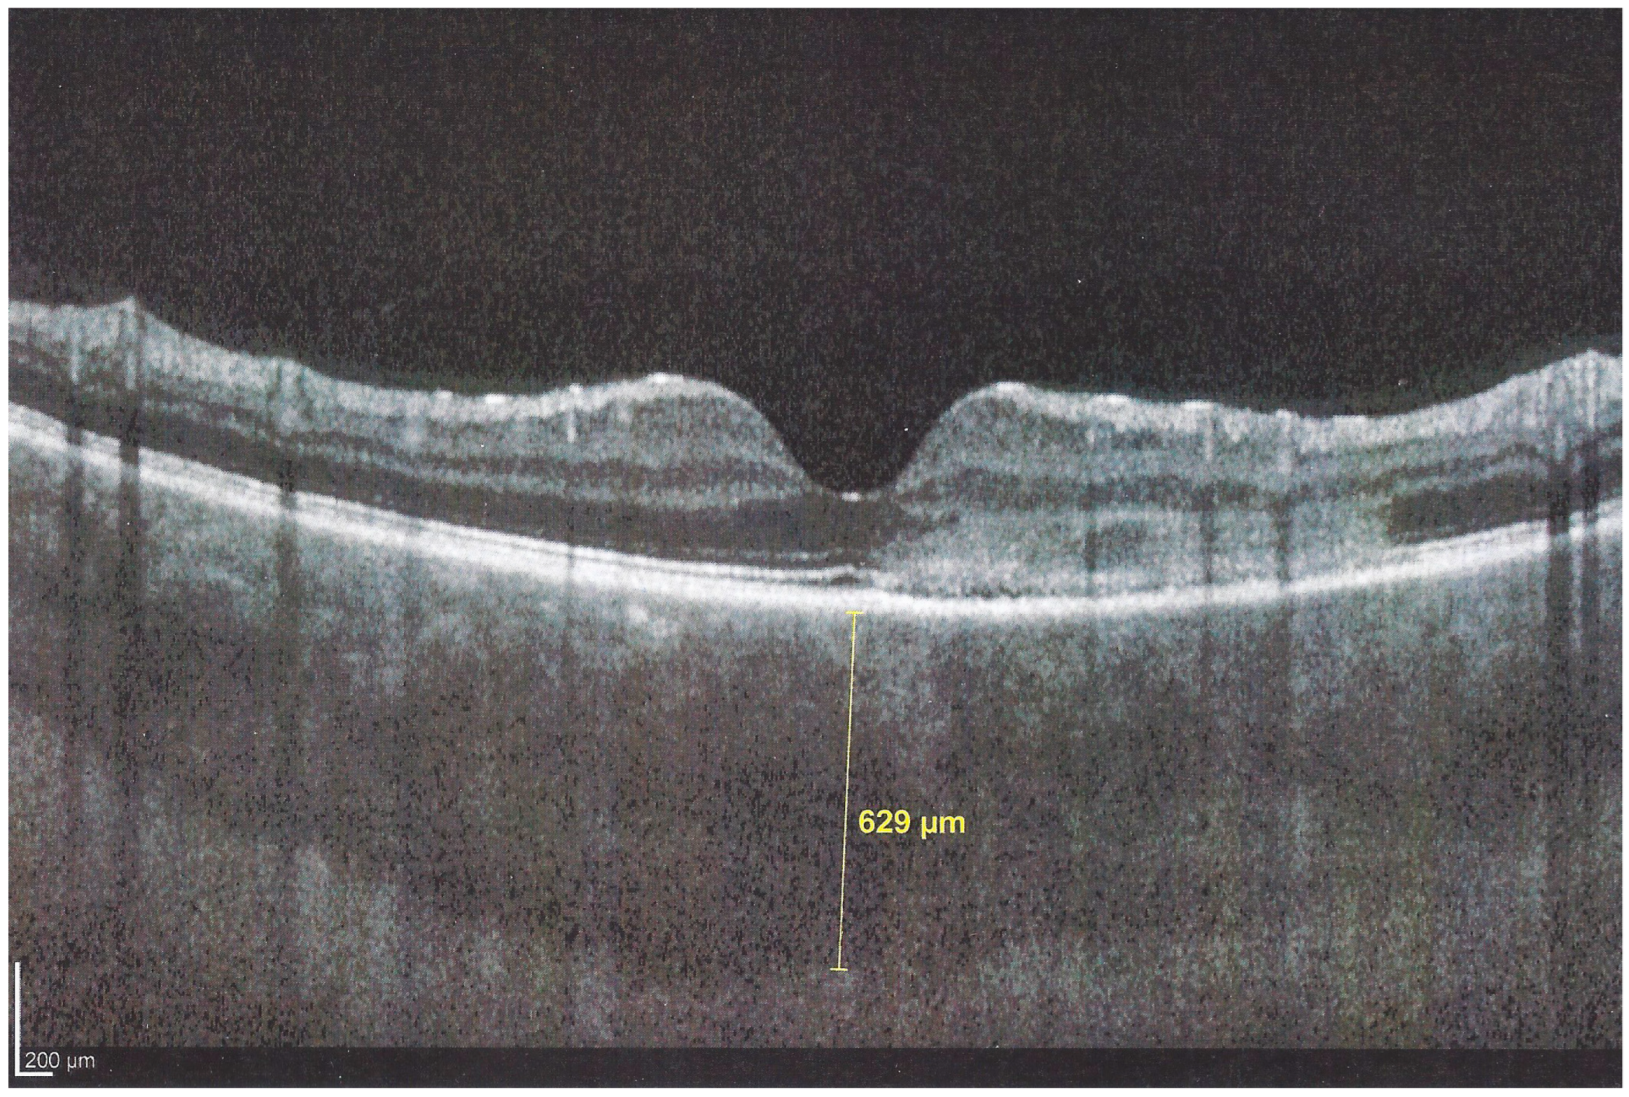

Figure 11. APMPPE/AMIC; EDI-OCT in the acute phase (same patient as Figure 5, Figure 6, Figure 7a, Figure 8 and Figure 9). In the acute phase, EDI-OCT shows an important thickening of the whole choroid with the calliper indicating a thickness of 629 µm.

In addition to choriocapillaris non-perfusion, in most acute cases, the entire choroid is thickened, which can be shown by enhanced depth imaging OCT (EDI-OCT) (Figure 11). In complement to ICGA, OCT angiography (OCT-A) shows areas of choriocapillary drop-out that correlate with the areas of ICGA hypofluorescence the analysed area being however, limited to part of the posterior pole and less precise than ICGA [5,7,25] (Figure 12).